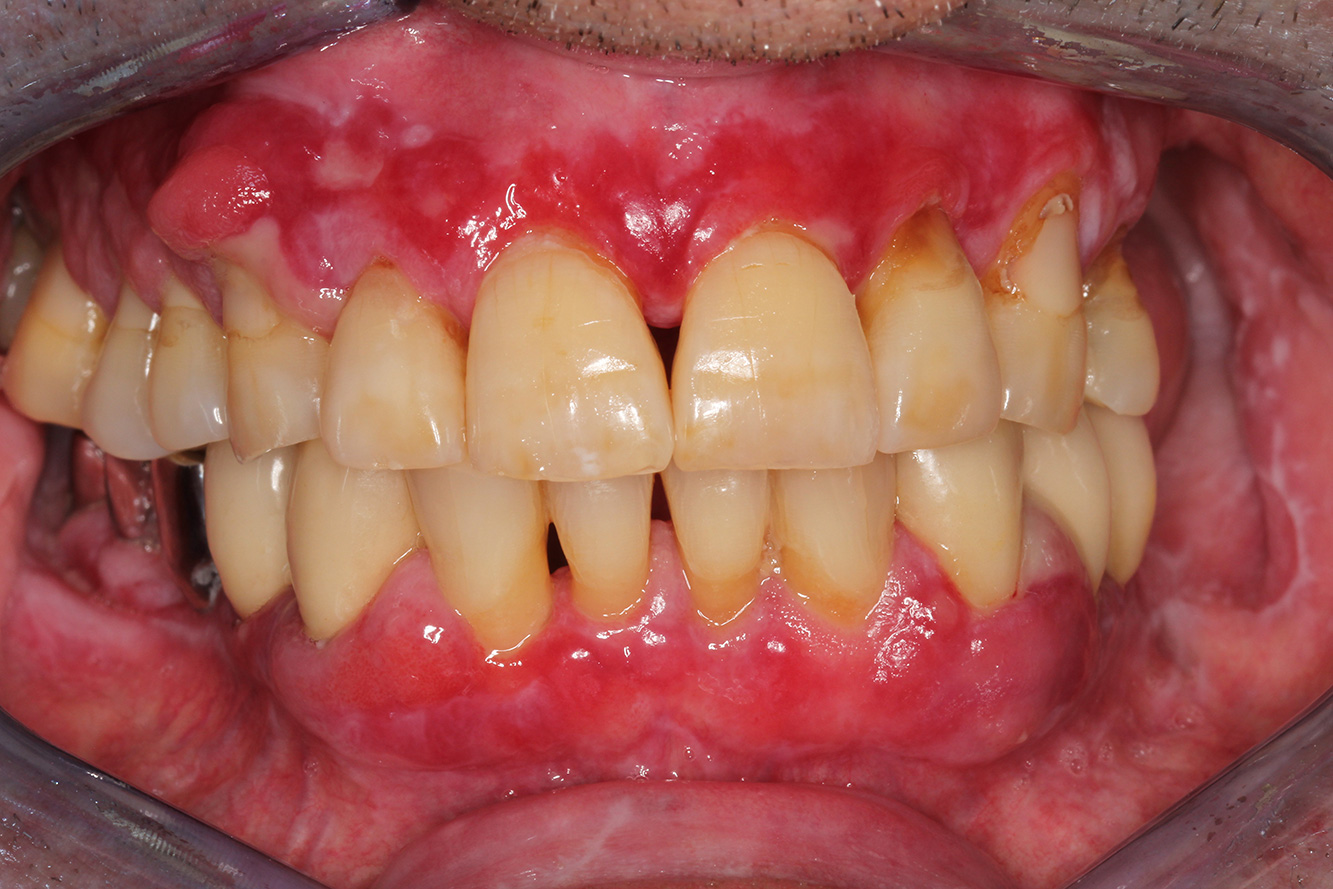

A 71-year old patient presents with having previously undergone a kidney transplant and with a history of hypertonia (high blood pressure). Due to his medical history, long-term medication with cyclosporine is required to suppress the immune system, as well as amlodipine to lower blood pressure. The patient also reports sensitive and bleeding gums. From an oral health perspective, the patient has undergone dental restoration and has eight missing teeth, pronounced gingival growth, and grade B, stage II periodontitis with active pockets and initial root caries on tooth 22. The caries risk assessment determines a moderate risk of caries (API 60). The following treatment recommendations can be determined for the prophylaxis session. more

The healthy patient with early periodontal disease